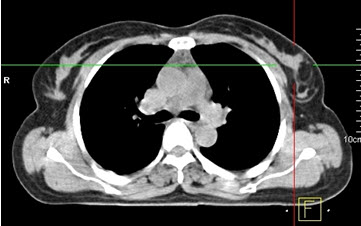

Hình 4 (a, b) cho thấy giá trị của PET/CT trong đánh giá giai đoạn của ung thư vú. Bệnh nhân Nguyễn Th. T. Tr., nữ, 63 tuổi, chẩn đoán là ung thư vú. Kết quả PET/CT toàn thân cho thấy nhiều tổn thương di căn hạch cổ, hạch trung thất, di căn 2 phổi, gan, xương tăng hấp thu FDG.

Hình 4a. Hình PET toàn thân thấy nhiều tổn thương hạch cổ, hạch trung thất (mũi tên vàng), phổi (mũi tên đỏ), gan (mũi tên tím) và xương (mũi tên xanh) tăng hấp thu FDG.

Hình 4b. Hình PET/CT ở mặt phẳng cắt ngang thấy tổn thương di căn phổi (mũi tên đỏ) và di căn gan (mũi tên da cam).